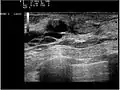

They are the most common cause of bloody nipple discharge in women age 20-40 and generally do not show up on mammography due to their small size. They may be detectable on ultrasound. A galactogram is the most definitive test but is somewhat invasive.